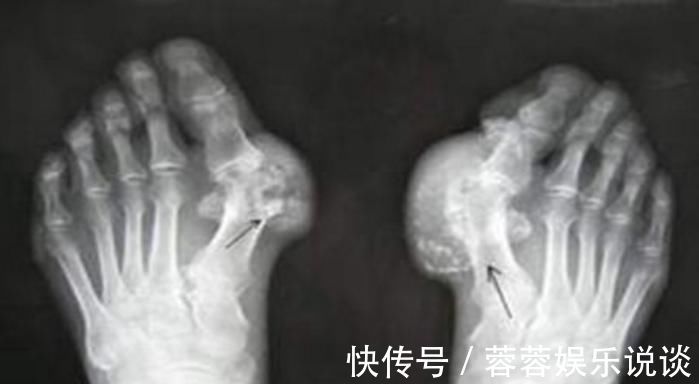

痛风的危害不仅仅是疼痛那么简单,若是长期置之不理,人体的关节组织会被侵蚀,最后形成痛风石。相信大家看到不少的案例,有的痛风患者关节组织变形石化,严重的影响着正常的生活,饱受着一生的痛苦折磨。

(4)慢性痛风石性痛风:痛风石是尿酸盐结晶沉积在关节内或关节周围组织,逐渐增大,形成突出于皮肤表面的黄白色结节。最后可导致关节变形,影响外观及功能。此时如果再不进行溶酸、排酸,很快就会并发其它更为严重的疾病。